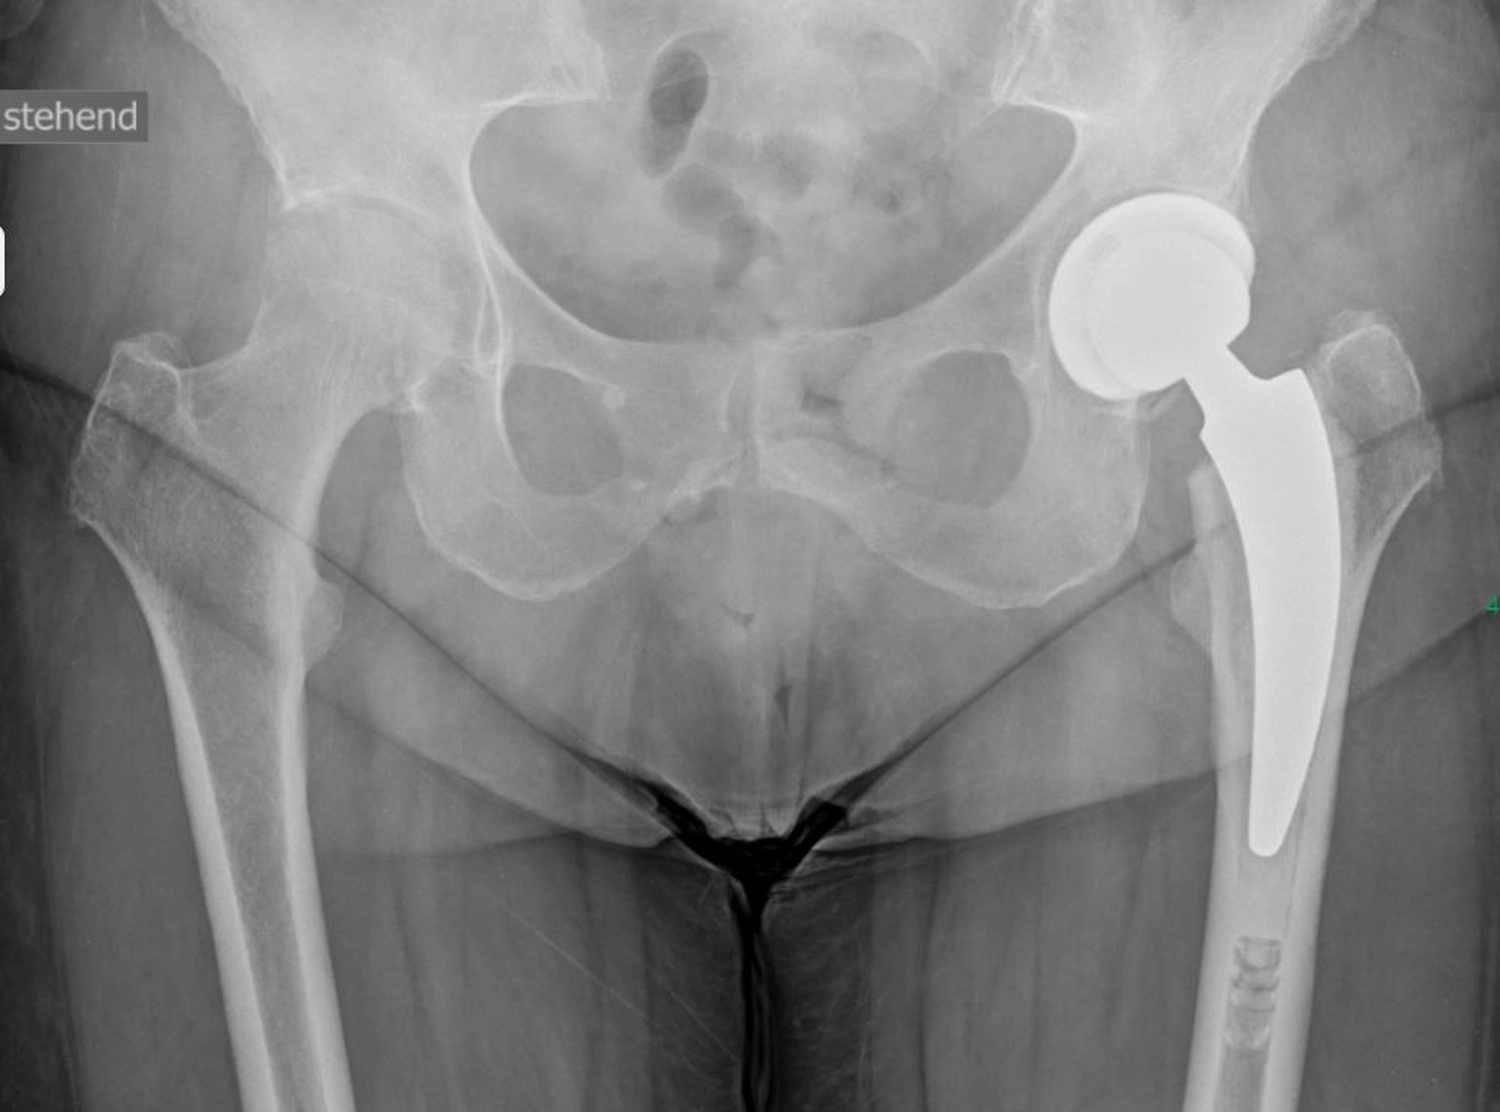

Ein künstliches Hüftgelenk ersetzt die geschädigten Teile des natürlichen Gelenkes. Es besteht aus mehreren Komponenten, die gemeinsam ein neues, stabiles und bewegliches Gelenk bilden. Die Pfanne wird in das Becken eingesetzt. Der Schaft wird im Oberschenkelknochen verankert. Der Prothesenkopf sitzt oben auf dem Schaft und bildet die „Kugel“ des Gelenkes und bewegt sich reibungsarm in der Pfanne.

Je nach Knochenqualität und Alter der PatientInnen werden zwei Verfahren angewendet.

Bei der zementfreien Prothese werden der Schaft und die Pfanne fest eingepresst und eingeschlagen. Der Knochen wächst in die aufgeraute Oberfläche ein und fixiert die Prothese dauerhaft.

Bei der zementierten Prothese werden die Prothesenteile mit einem speziellen Knochenzement befestigt. Der Vorteil besteht in einer sofortigen Stabilität, besonders geeignet bei älteren oder osteoporotischen PatientInnen.

Daneben gibt es sog. Hybridverankerungen, z. B. Pfanne zementfrei, Schaft zementiert.

Moderne Prothesen, wie wir sie hier in Stenum verwenden, sind so konstruiert, dass sie reibungslos, stabil und langlebig funktionieren, meist über viele Jahre bzw. Jahrzehnte (15–20 Jahre).

Dank der modernen Materialien und gewebeschonenden Techniken des Einbringens, (minimalinvasiver Zugang) ist die Hüft-TEP heute ein sehr erfolgreicher Eingriff, der vielen Menschen eine deutliche Verbesserung ihrer Lebensqualität ermöglicht.